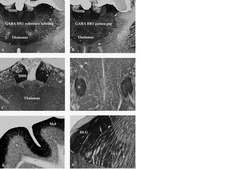

Detect GABA B Receptor R1 using this Anti-GABA B Receptor R1 Antibody validated for use in WB, IH.

Immunohistochemistry: Working dilution of 1:3,000 in free floating mouse brain tissue.